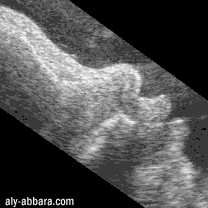

Fœtus à 37 semaines d'aménorrhée

La bouche vue par coupe sagittale médiane avec les mouvements

de succion auxquels on remarque la participation des lèvres

et de la langue